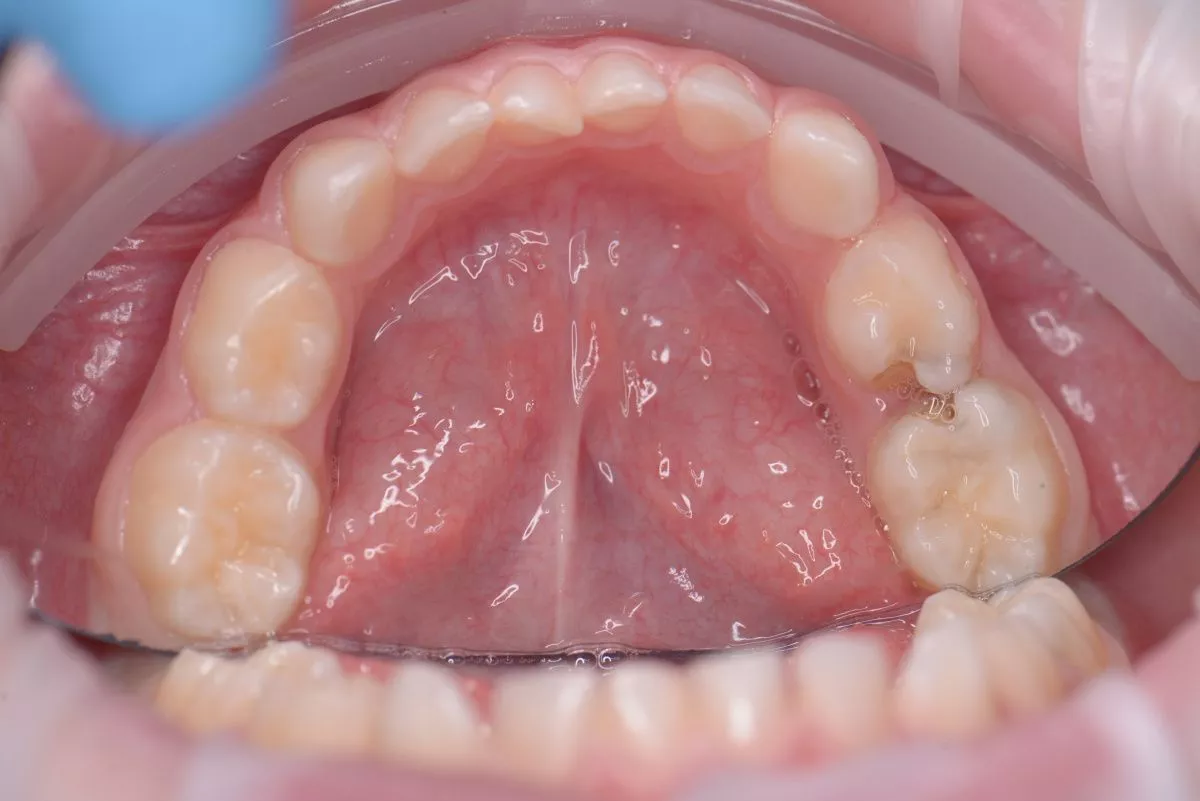

етская стоматология под наркозом Москва. Лечение кариеса, пульпита и установка металлических коронок детям - до процедуры

етская стоматология под наркозом Москва. Лечение кариеса, пульпита и установка металлических коронок детям - после процедуры